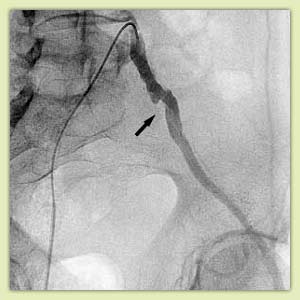

Ангиограммы до и после стентирования:

|

Сужение подключичной (черная стрелка) и позвоночной (белая стрелка) артерий |

То же после стентирования подключичной и дилятации позвоночной артерии. |